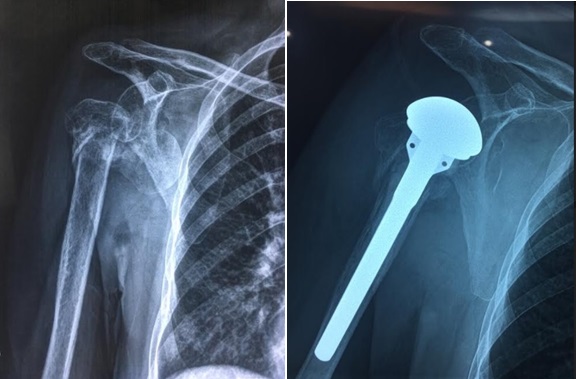

Tin theo lời thầy lang chữa bệnh, bà C. đi đắp thuốc, bó lá chữa gãy trật khớp vai suốt 1 tháng. Đến khi thấy chỗ khớp vai sưng nề, đau tăng lên, bà được người nhà đưa đến Viện chấn thương chỉnh hình, Bệnh viện Việt Đức, tình trạng của bà trở nên quá nặng phải phẫu thuật thay khớp vai, nếu không...